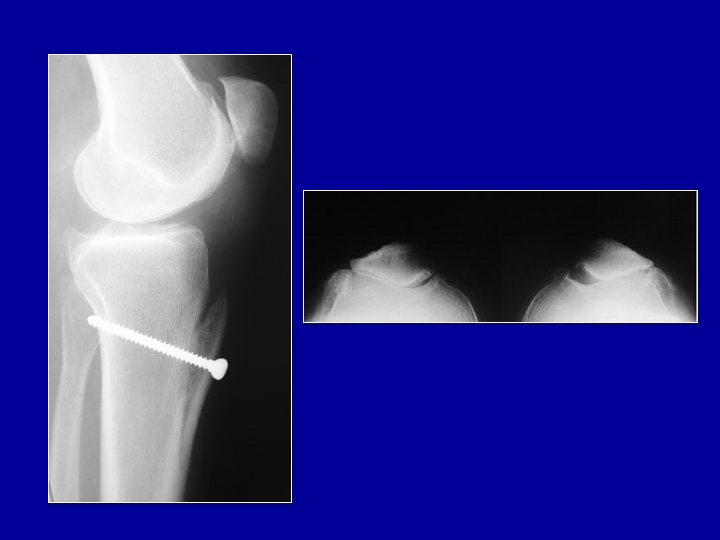

Transposition de la tubérosité tibiale en dedans et en avant (Maquet)

Opération de recentrage avec avancement de la tubérosité L’avancement (Maquet) peut diminuer favorablement les pressions Les résultats sont inconstants